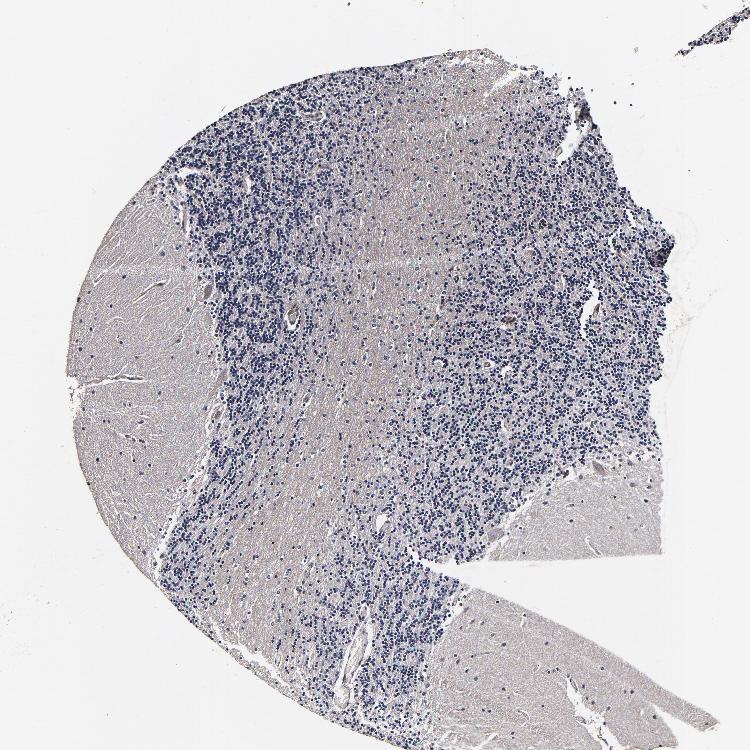

BRAIN CEREBELLUM Show tissue menu

CEREBELLUM - Expression summary

CEREBELLUM - Antibody stainingi

Antibody staining in the annotated cell types in the current human tissue is reported as not detected, low, medium, or high, based on conventional immunohistochemistry profiling in selected tissues. This score is based on the combination of the staining intensity and fraction of stained cells.

Each image is clickable and will lead to virtual microscopy that enables deeper exploration of all samples and also displays staining intensity scores, fraction scores and subcellular localization as well as patient and tissue information for each sample.

Antibody HPA040390Antibody CAB002611

Purkinje cells LowNot detected

Cells in granular layer MediumNot detected

Cells in molecular layer Not detectedNot detected